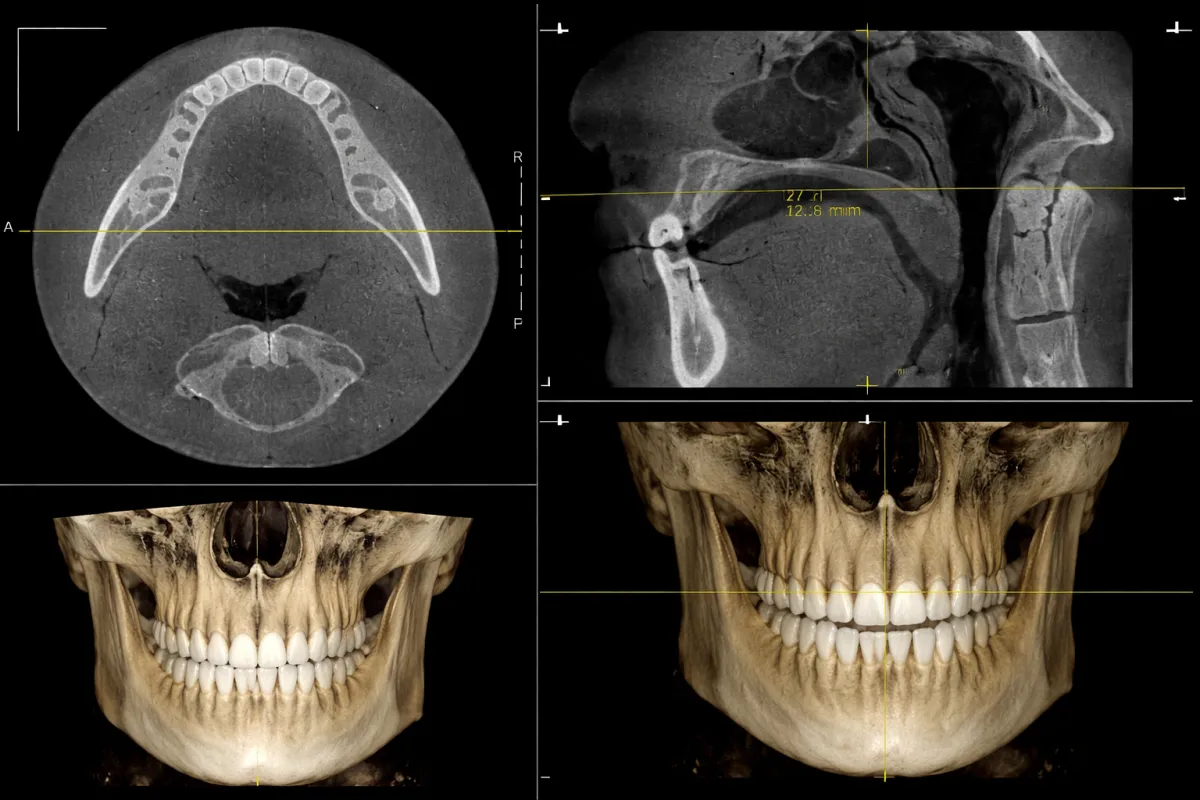

Expanding Wallets With Palates: The Evidence Problem with MARPE and Palatal Expansion in Treating TMJ Problems

Bite interventions may not be needed when addressing jaw pain. TMD may be the leading cause.